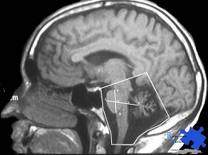

- Imagen de resonancia magnética.

- Tomografía computarizada.